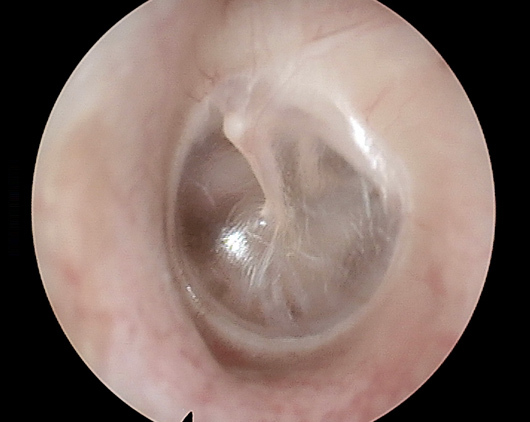

正常な鼓膜

右鼓膜正常所見

これが正常鼓膜の写真です。真珠のような色と光沢をしています。この奥にある空間が中耳です。